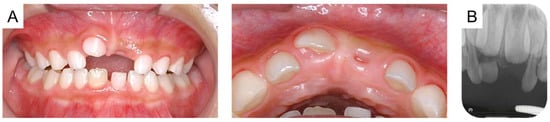

Intraoral photographs and radiographs are shown in Figure 1. The maxillary right primary central incisor was positioned higher than the central incisor on the left side, and a metallic percussion sound was noted. A periapical radiograph revealed external root resorption of the maxillary right primary central incisor, and the periodontal ligament appeared unclear. Additionally, the maxillary left primary central incisor exhibited external root resorption and obstruction of the pulp chamber. However, there was no difference in positioning between the unerupted maxillary permanent central incisors.

Figure 1. Initial examination at the age of 4 years and 8 months: (A) intraoral photographs and (B) periapical radiograph.